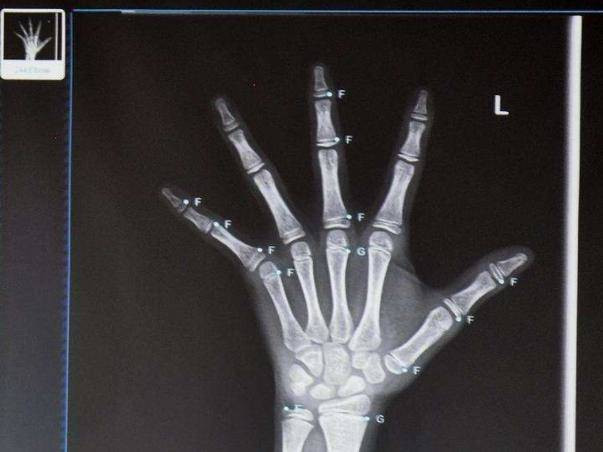

Sau khi được kiểm tra y tế, các bác sĩ kết luận rằng từ những kết quả đo tuổi xương và nội tiết thì khả năng phát triển của bé đã “đóng lại”. Tuổi xương của bé mãi mãi sẽ dừng lại ở tuổi 13 và không cao thêm nữa.

Tuổi xương của bé mãi mãi sẽ dừng lại ở tuổi 13 và không cao thêm nữa.